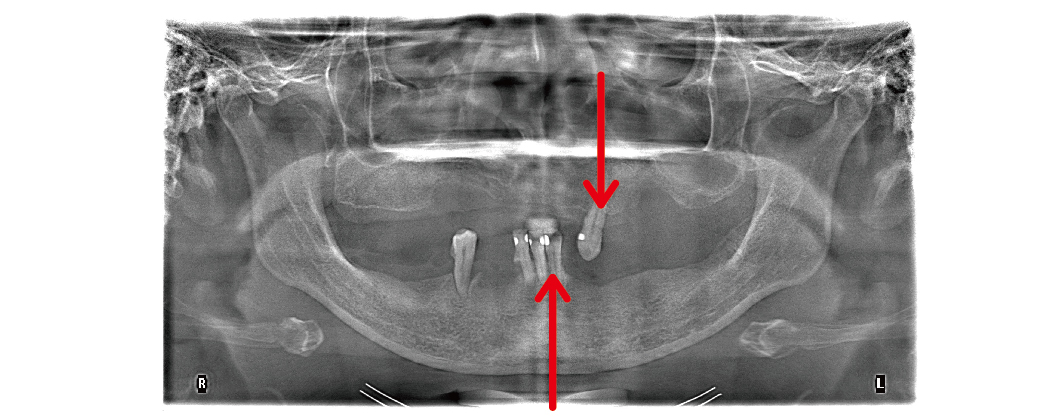

All-on-4/6 全口重建是一個很完整、系統性的治療流程,我們在開始之前,會先幫您做詳細的評估,包括拍攝X光、3D斷層掃描,還有口內外的檢查,來了解目前牙齒、骨頭和牙周的狀況,接下來,我們會根據您的需求和生活習慣,討論最適合您的治療方式。

▲初診的環口式X光片檢查,上、下顎嚴重缺牙